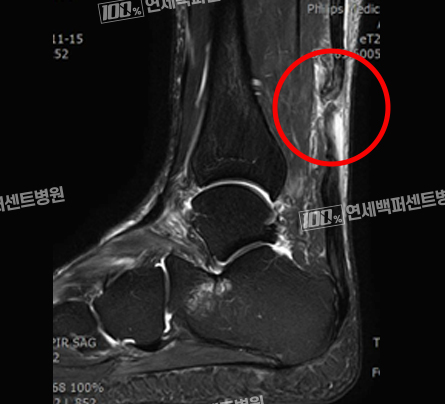

수술 전 MRI 영상

완전히 파열되어 절단된

아킬레스건

최소침습 재건술

평균 3cm 정도의 최소침습 아킬레스 재건술

특수봉합 테크닉으로 기존의 10cm 이상의

절개창을 획기적으로 줄여서 수술후

통증, 흉터, 감염 위험을 낮추었습니다!